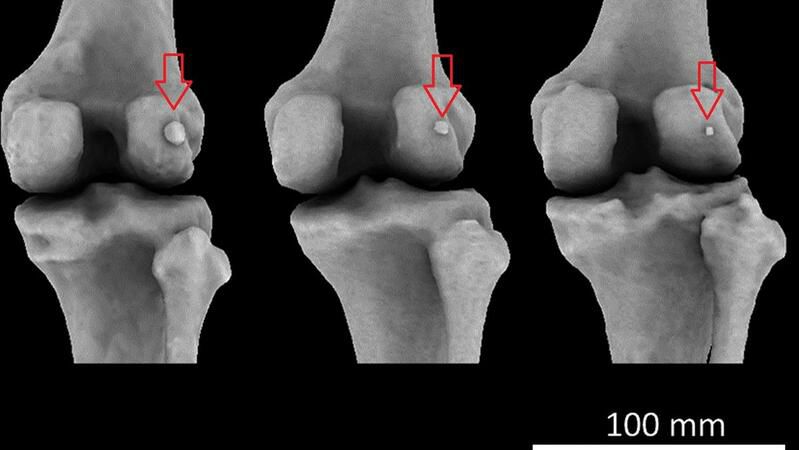

La fabela es un hueso sesamoide, es decir, un hueso redondeado, que crece en el tendón de un músculo (el mayor es la patela, o rótula). La fabela es mucho más pequeña que esta y se sitúa detrás de la rodilla. Por su tamaño y por lo poco común de su presencia, a veces en las radiografías se lo confunde con un fragmento óseo o un cuerpo extraño.

De acuerdo con el estudio, publicado en el Journal of Anatomy, en 1918 el 11,2% tenía ese hueso. Un siglo después, su presencia es tres veces más común, y se lo detecta en el 39% de la población. El estudio se llevó a cabo a partir de los análisis de rayos X, disecciones anatómicas y -más recientemente- resonancias magnéticas.